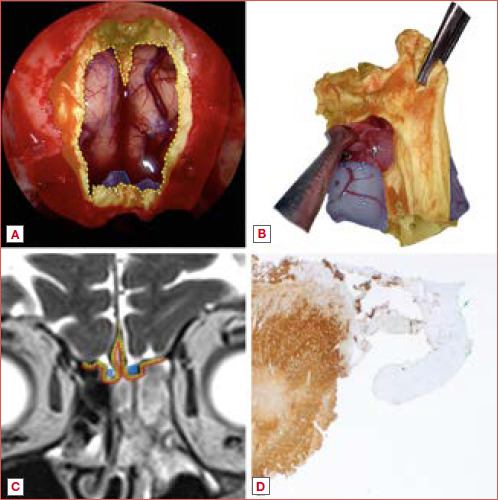

Abstract Image